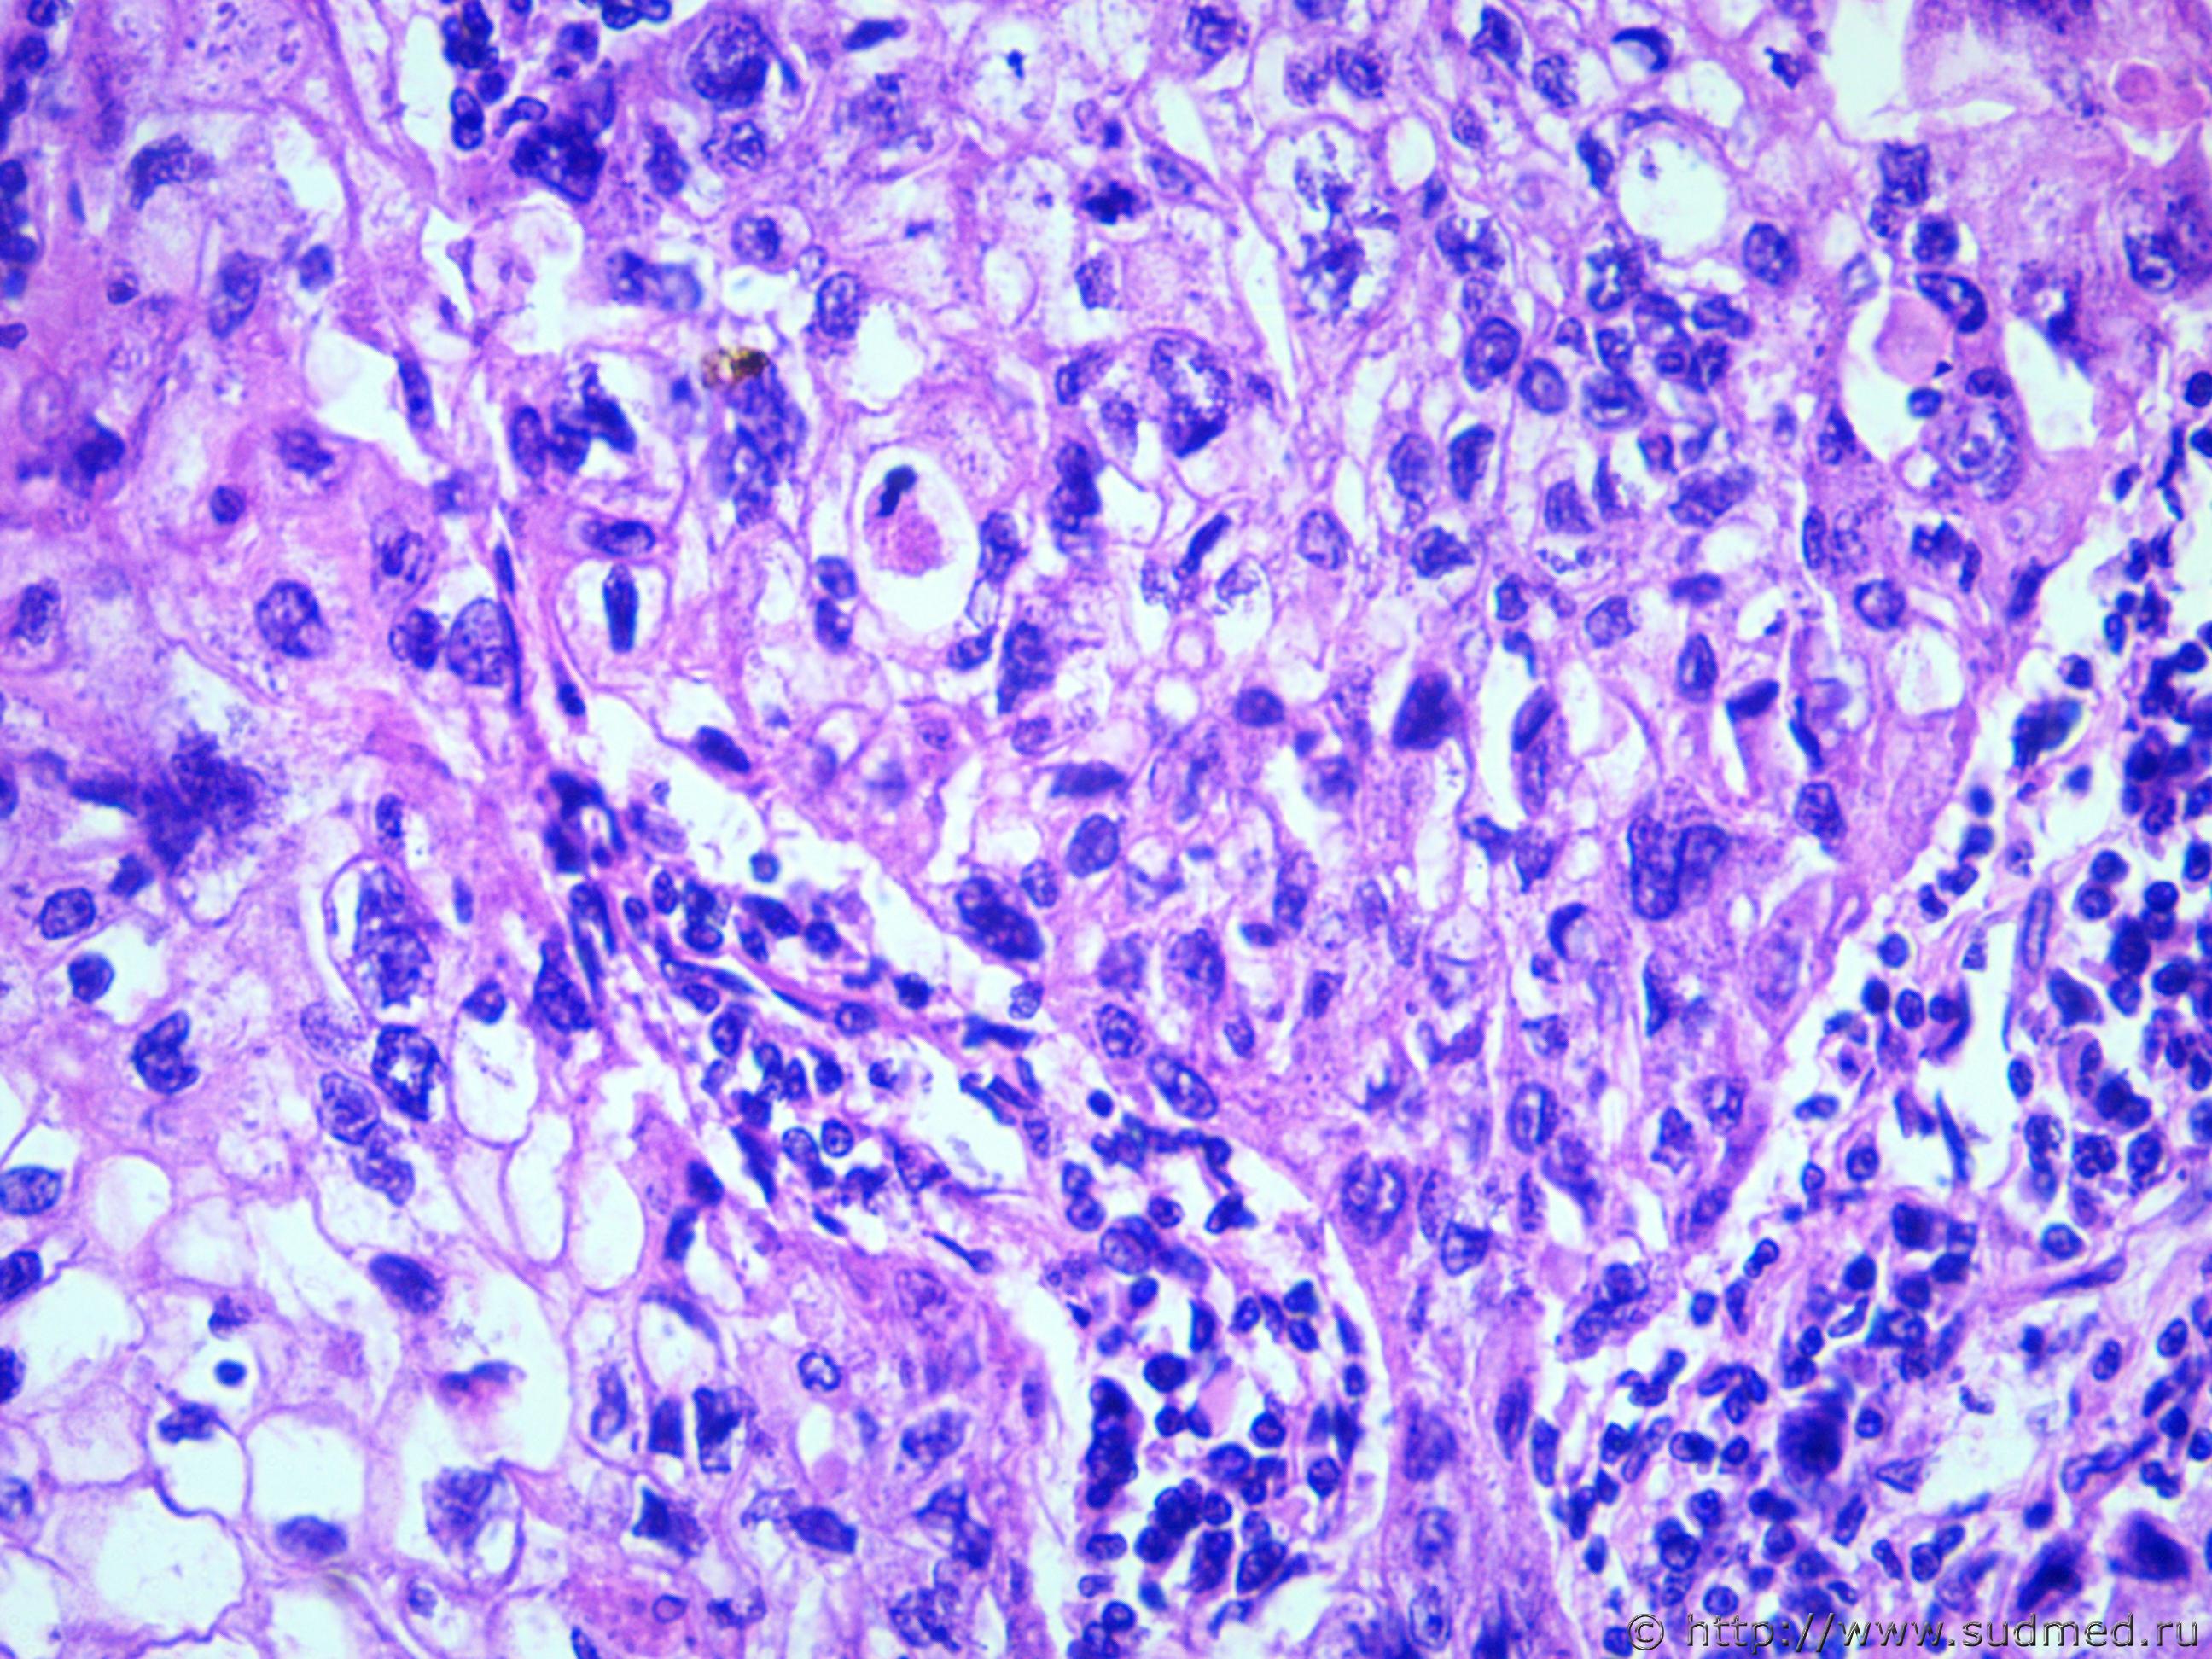

Похоже на метастаз плоскоклеточного рака в л/у.

Тимома по типу В3. -периваскулярные щели инфильтрированы лимфоцитами - наблюдается некроз ,тканевой,клеточный и ядерный атипизм, гликогенофильность ввиде эозинофилии в строме и местами в цитоплазме эпителии опухоли. Возможно при жизни страдал миастенией...

Вы видите трёхлопастные митозы ? Этот патологический митоз наиболее часто встречается у плоскоклеточных раков.

В первом вашем фото веретеноклеточная структура, а во втором фото плоскоклеточная структура согласен. Но в фото ТС анапластически тип( крупные светлоклеточные, округлыем плоские со смещением ядра с единичными патологическими митозами). Не исключается учитывая некроза метастатический генез. Но ТС утверждает только в средостении и больше нигде не видит. Однако в опухоли тимомы типа 3 периваскулярное расположение опухоли( вокруг синусоидов или бывает полисадность и перицитарность) указывает за тиомму типа 3.

Добрый день, выяснили у танатолога что опухоль располагалась между дугой аорты и правым легким, прилежала к трахее, пищеводу отдельным узлом

Судя по локализации,тимома "отпадает".